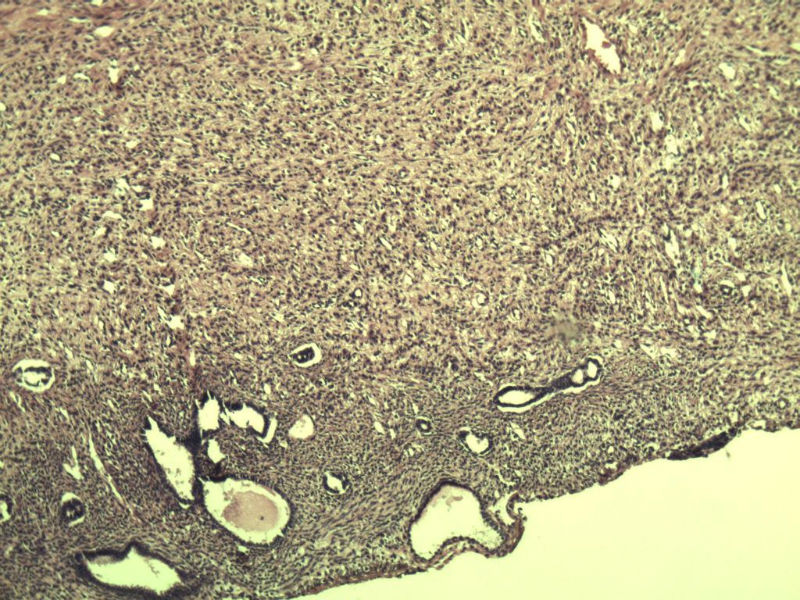

女,57岁,全切子宫一个,宫体体积 9 × 8 × 7 cm3,肌壁厚 2.5 cm,内膜菲薄,部分区域增厚达 0.4 cm(约3*2.5cm区域)。 请问各位老师  这个可以诊断子宫内膜癌了吧?      深肌层没有看到浸润。

患者因"发现下腹部包块1月多"入院  宫体体积 9 × 8 × 7 cm3,肌壁厚 2.5 cm,内膜菲薄,部分区域厚 0.4 cm(约3*2.5cm)。宫颈结构不清,长约 2.5 cm,表面欠光滑。临床诊断宫颈宫腔积液.

宫内膜样腺癌

筛状、迷路样结构

间质消失或者纤维性间质

子宫内膜样腺癌

高分化子宫内膜样癌。浸润浅肌层(深度<1/3肌层)。根据FIGO2009分期,子宫内膜癌局限于内膜层和<1/2肌层,都属于IA期。二者处理不再区别对待。